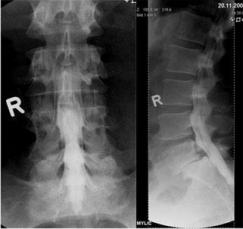

Dies sind Röntgenaufnahmen von derselben Stelle, die in verschiedenen Körperpositionen aufgenommen werden, bei der Wirbelsäule zumeist in Vor- und Rückneigung. Sie dienen der Diagnose von Gleitwirbeln.

Aufnahmen von der Wirbelsäule zur Beurteilung von Veränderungen am Knochen, vor Operationen, zum Ausschluß von Knochenbrüchen und zur Verlaufskontrolle. Eine spezielle Vorbereitung der Patienten ist nicht notwendig. Moderne Röntgengeräte fertigen solche Aufnahmen mit einer geringen Strahlendosis an. Für alle, die sich genauer über die Auswirkung von Strahlen informieren wollen, empfiehlt sich ein Blick in Wikipedia.

Im Röntgenbild sieht man vergrößerte und deformierte Wirbelgelenke.

Ein Gleitwirbel liegt vor, wenn sich ein Wirbel gegenüber einem anderen verschoben hat, diese also nicht mehr in einer Linie stehen.

Da ein Wirbelgleiten zu einer Verengung des Wirbelkanals führt, sind die Beschwerden mit denen der Spinalkanalstenose vergleichbar: Schmerzen und Gangstörungen.